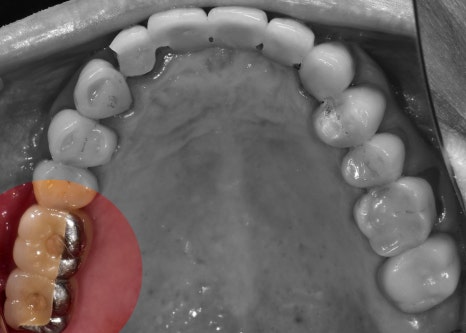

뼈와 다 아물게 되면, 오른쪽 사진에서

보실 수 있는 것 처럼 지르코니아 크라운이

연결이 되면 모든 시술은 끝나게 됩니다.

이 분의 경우에는, 만 65세가 넘으셨기 때문에

보험 임플란트 적용이 가능했었습니다.

따라서, 상악에는 지르코니아 크라운이 아닌

PFM 크라운으로 셋팅을 해드렸으며

하악에만 지르코니아 크라운이 연결되었습니다.